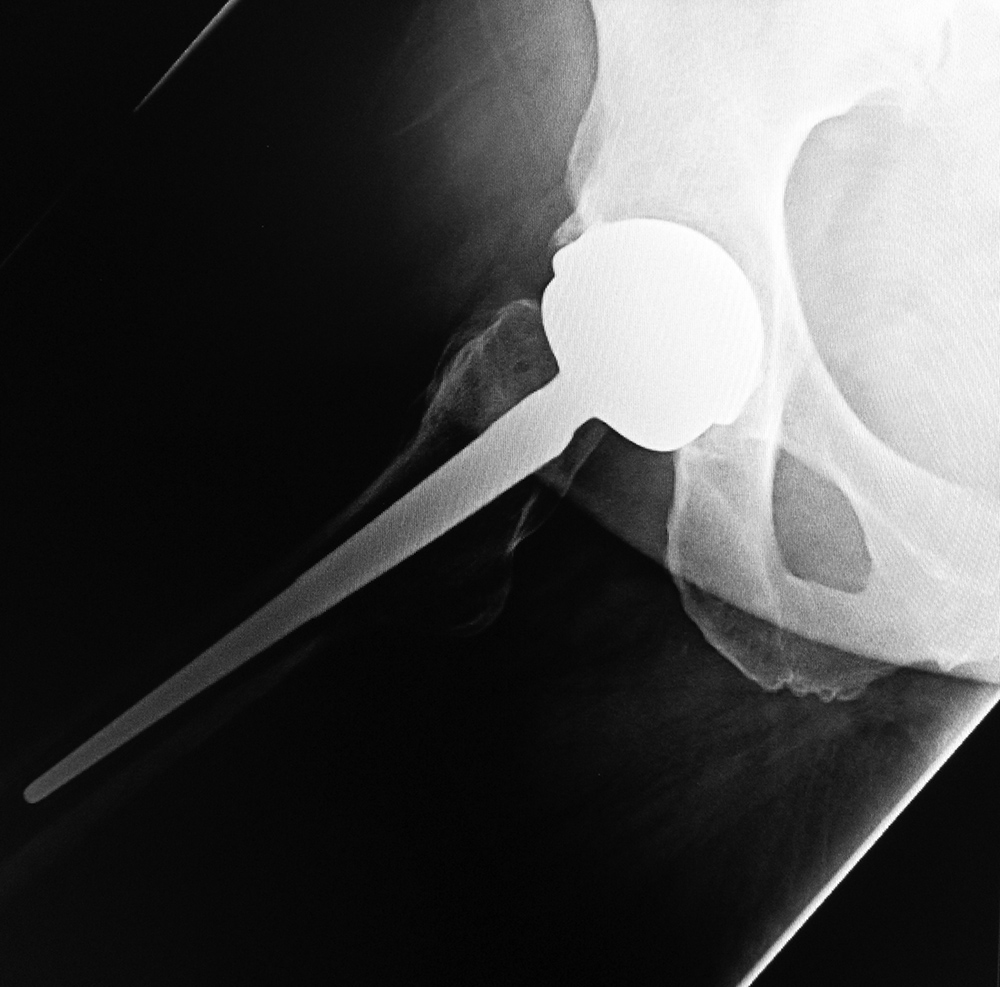

Hip instability and dislocation is a feared complication of hip replacement. Fortunately, dislocation is a

relatively uncommon complication in primary total hip arthroplasty occurring in approximately 0.4%–0.8%

of cases. It is, unfortunately, much more common after hip revision arthroplasty occurring in up to 16% of cases (Galante, 1998). Hip dislocation occurring within the first three months after surgery is presumed to be caused by laxity of the immature pseudocapsule of the joint and laxity of the soft tissues (Mulcahy, 2012). In our experience most prosthetic hip dislocations are in a posterior direction (figure: posterior total hip arthroplasty dislocation). Late dislocation is often the result of trauma. Early dislocation may often be successfully treated with non-operative reduction, while a late dislocation or a traumatically induced dislocation often require surgical correction.